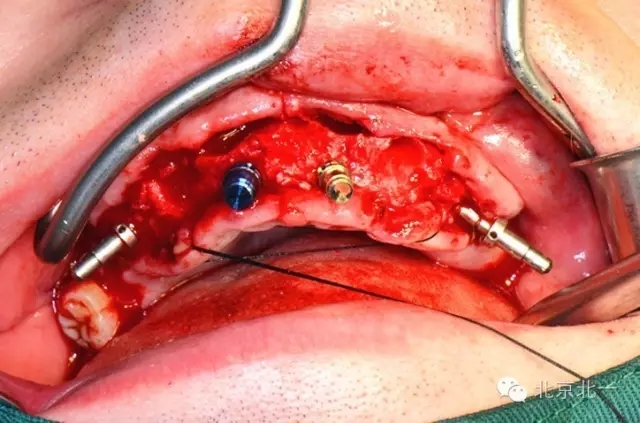

圖三、四:術(shù)中植入四枚植體,長度15mm。角度復(fù)合基臺